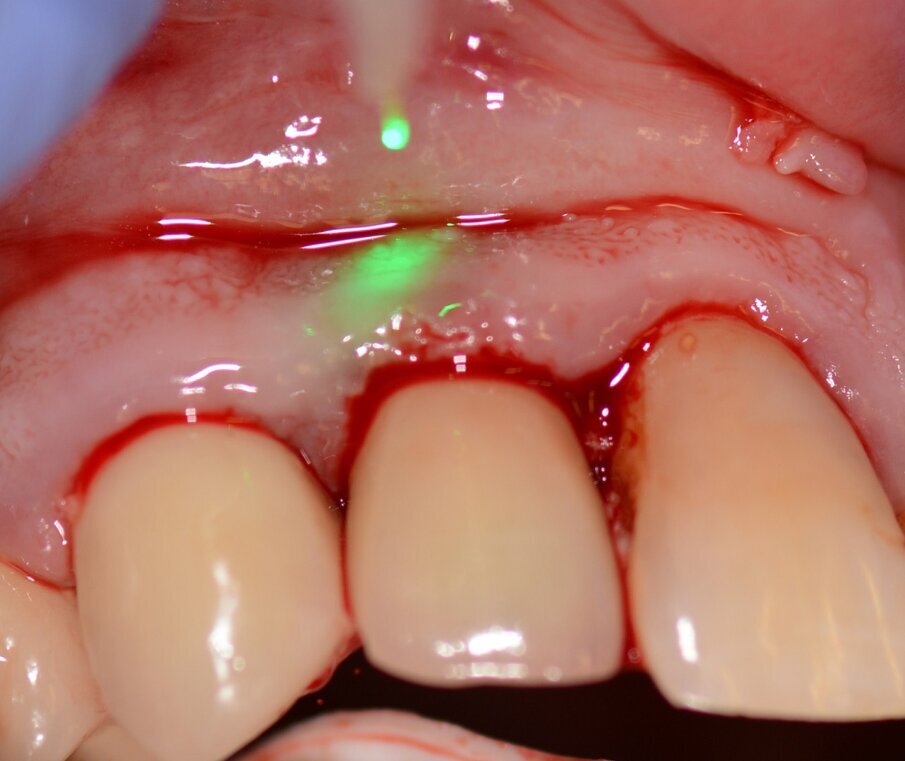

Figs. 4 & 5: Use of the Er:YAG laser Varian tip for granulation tissue removal, implant surface decontamination...

...and surface ablation of infected bone.

Fig. 6: Photo-biomodulation with the Nd:YAG laser.

Fig. 10: Granulation tissue removal with Er:YAG laser.

Fig. 16: Granulation tissue removal with Er:YAG.